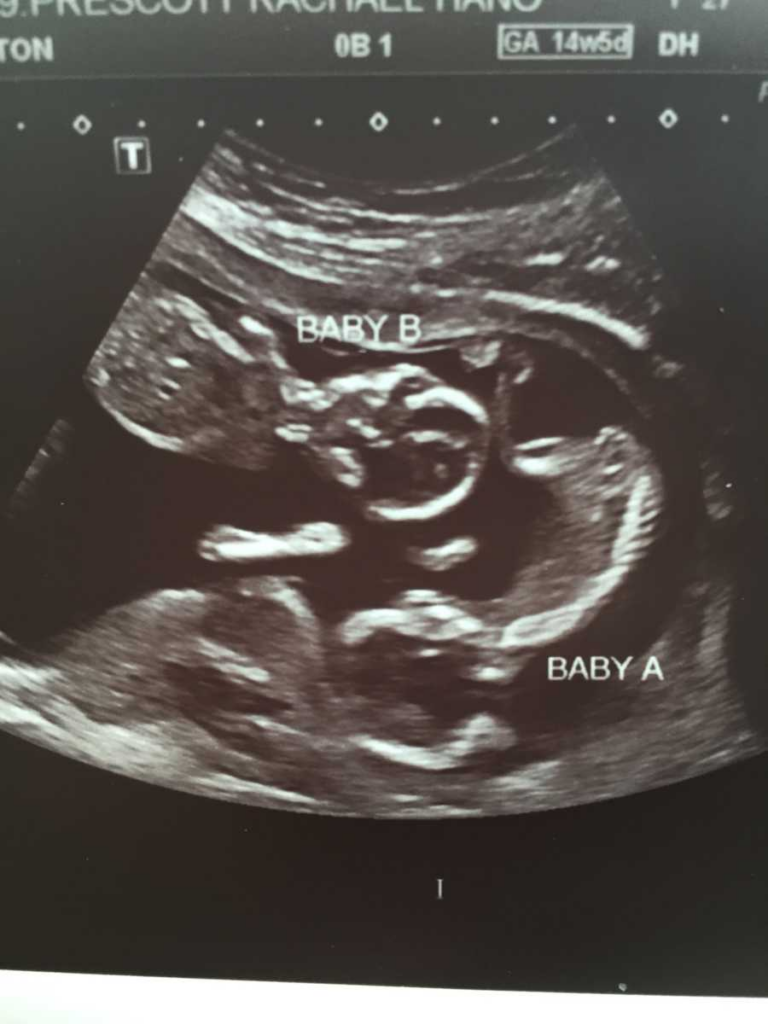

But at their first midwife appointment, everything changed, another two tiny heartbeats. Cody laughed in disbelief while Rachael sat stunned. They’d need a bigger car, a new crib, maybe a new house. She could barely believe it. Two babies. During another ultrasound, that happiness faded a few weeks later as technicians avoided eye contact when the two identical girls appeared on the screen, and the news of both babies having congenital heart disease came. They needed open-heart surgery soon after their birth. Doctors also warned them about girls having Down syndrome.